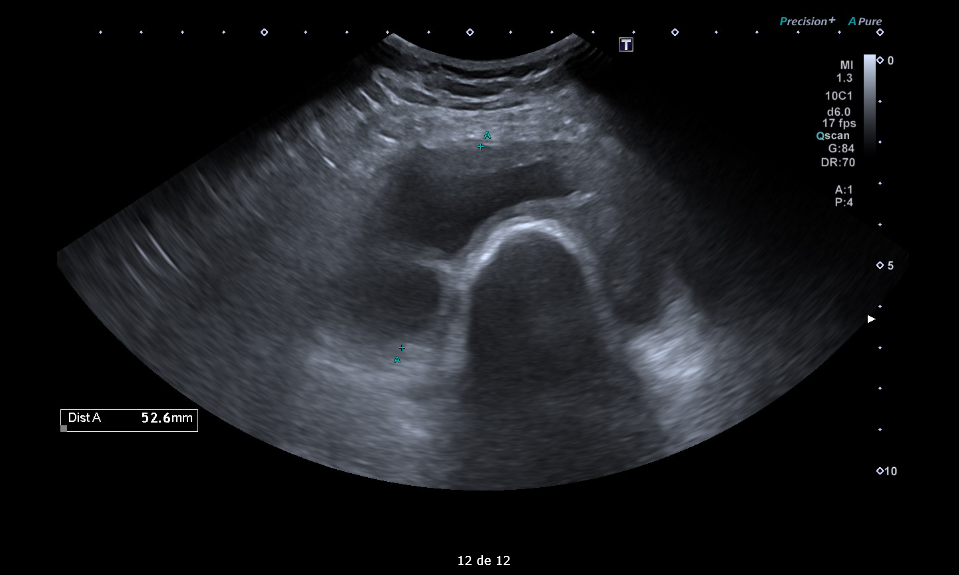

Masa sólida de partes blandas de 5 x 9 x 14 cm en compartimento femoral anterior, en profundidad al recto femoral y vastos medial y lateral. Engloba desde el tercio medio de la diáfisis hasta la rótula. Presenta polos sólidos vascularizados y zonas quísticas/necróticas.

RMN de rodilla: gran masa sólido-quística de 19 x 9,7 x 5,8 cm intraarticular centrada en el receso suprapatelar que se extiende por espacio articular femorotibial hasta el compartimento posterior de la rodilla.